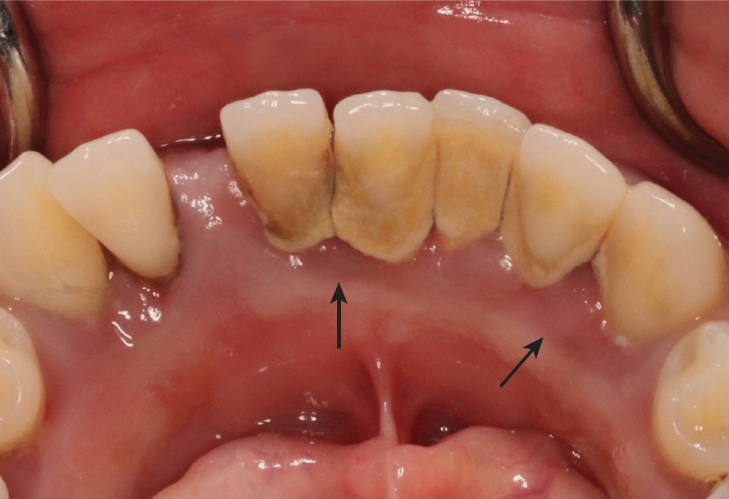

characteristics of gingivitis

some reversible tissue damage

clinical: red, swollen (edematous), bleeding likely, sulcus depth 3mm+

histological: JE at CEJ, supra-gingival fiber destruction, alveolar bone intact, periodontal ligament intact

cyanotic gingiva

reddish-blue color of gingivitis

blood flow increases → blood vessels become congested → slows flow of oxygenated blood to tissues and the flow of unoxygenated blood away from the tissues → unoxygenated blood pools in the gingival tissues